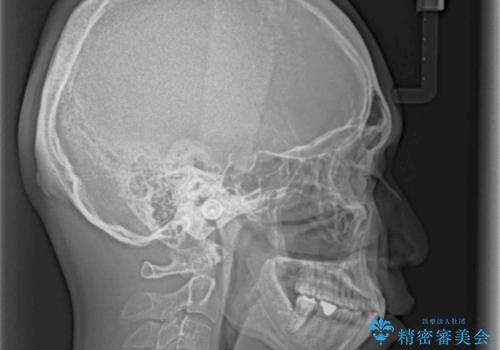

口が少し閉じにくい インビザラインによる非抜歯矯正

- 口元の突出感を治したいとのことで来院された患者様です。

上下顎ともにIPR(歯と歯の間を削る)と歯列全体の拡大によって口元が引っ込むように設計し、インビザラインにより治療を行うこととしました。

抜歯をして口元を下げなければならないほど出っ歯ではなかったため、少しずつ治療ゴールを変更しながら仕上げていきました。

気になっていた前歯の飛び出した印象は、最終的にはスッキリと引っ込み、大変満足していただきました。